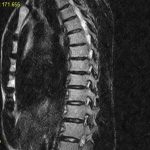

Заболевание медленно, но неотвратимо наносит удар. Если рассмотреть шейный остеохондроз на рентгене, можно обнаружить, что межпозвонковый диск подвержен деформации. Это вызвано потерей его эластичности. Остеохондроз шеи нередко является причиной обмороков.

Расслоение межпозвоночных дисков вызывает грудной остеохондроз (фото 4). Постепенно снижая свою высоту, диски ущемляют межреберные нервы. Однако симптомы остеохондроза грудного отдела наблюдаются крайне редко. Это благодаря мощной физиологической реберной фиксации.

Грудной остеохондроз поражает чаще верхнегрудные позвонки, вызывая их деформацию. Не следует путать сколиоз позвоночника, являющегося асимметрической особенностью. Симптомы грудного остеохондроза проявляются в различной степени.

Симптомы остеохондроза этого вида характерны различными болевыми ощущениями. Остеохондроз поясничного отдела (фото 7) наиболее ощутим в утреннее время. Ближе к обеду, когда больной расходится, боли притупляются. Ярким примером может служить шпора на пятке, отпускающая боль при аналогичной ситуации. Остеохондроз на рентгене точно показывает, чем вызван болевой синдром. Это миелопатия, радикулопатия, либо иная причина.